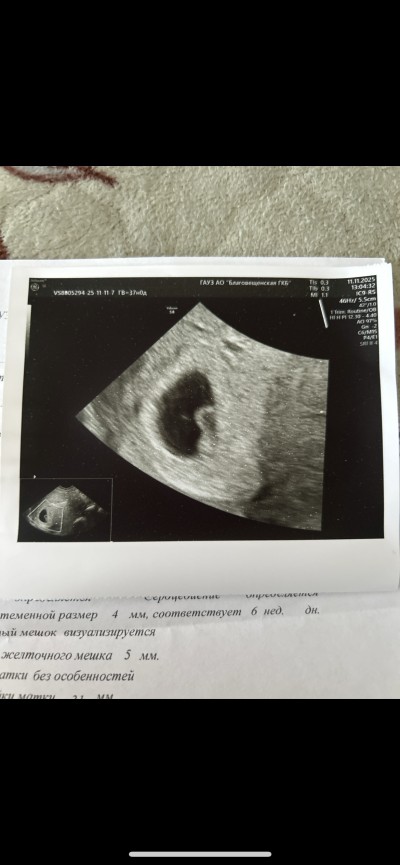

6+4 haftalik vajinal ultrasondan bakildi. Tahminde buluna bilirmisiniz lutfen 💕

Ben Rusyada yasiyorum , ilk ultrasonumdu , direk vajinal ultrason yapti. Haftasinida o zaman soyledi